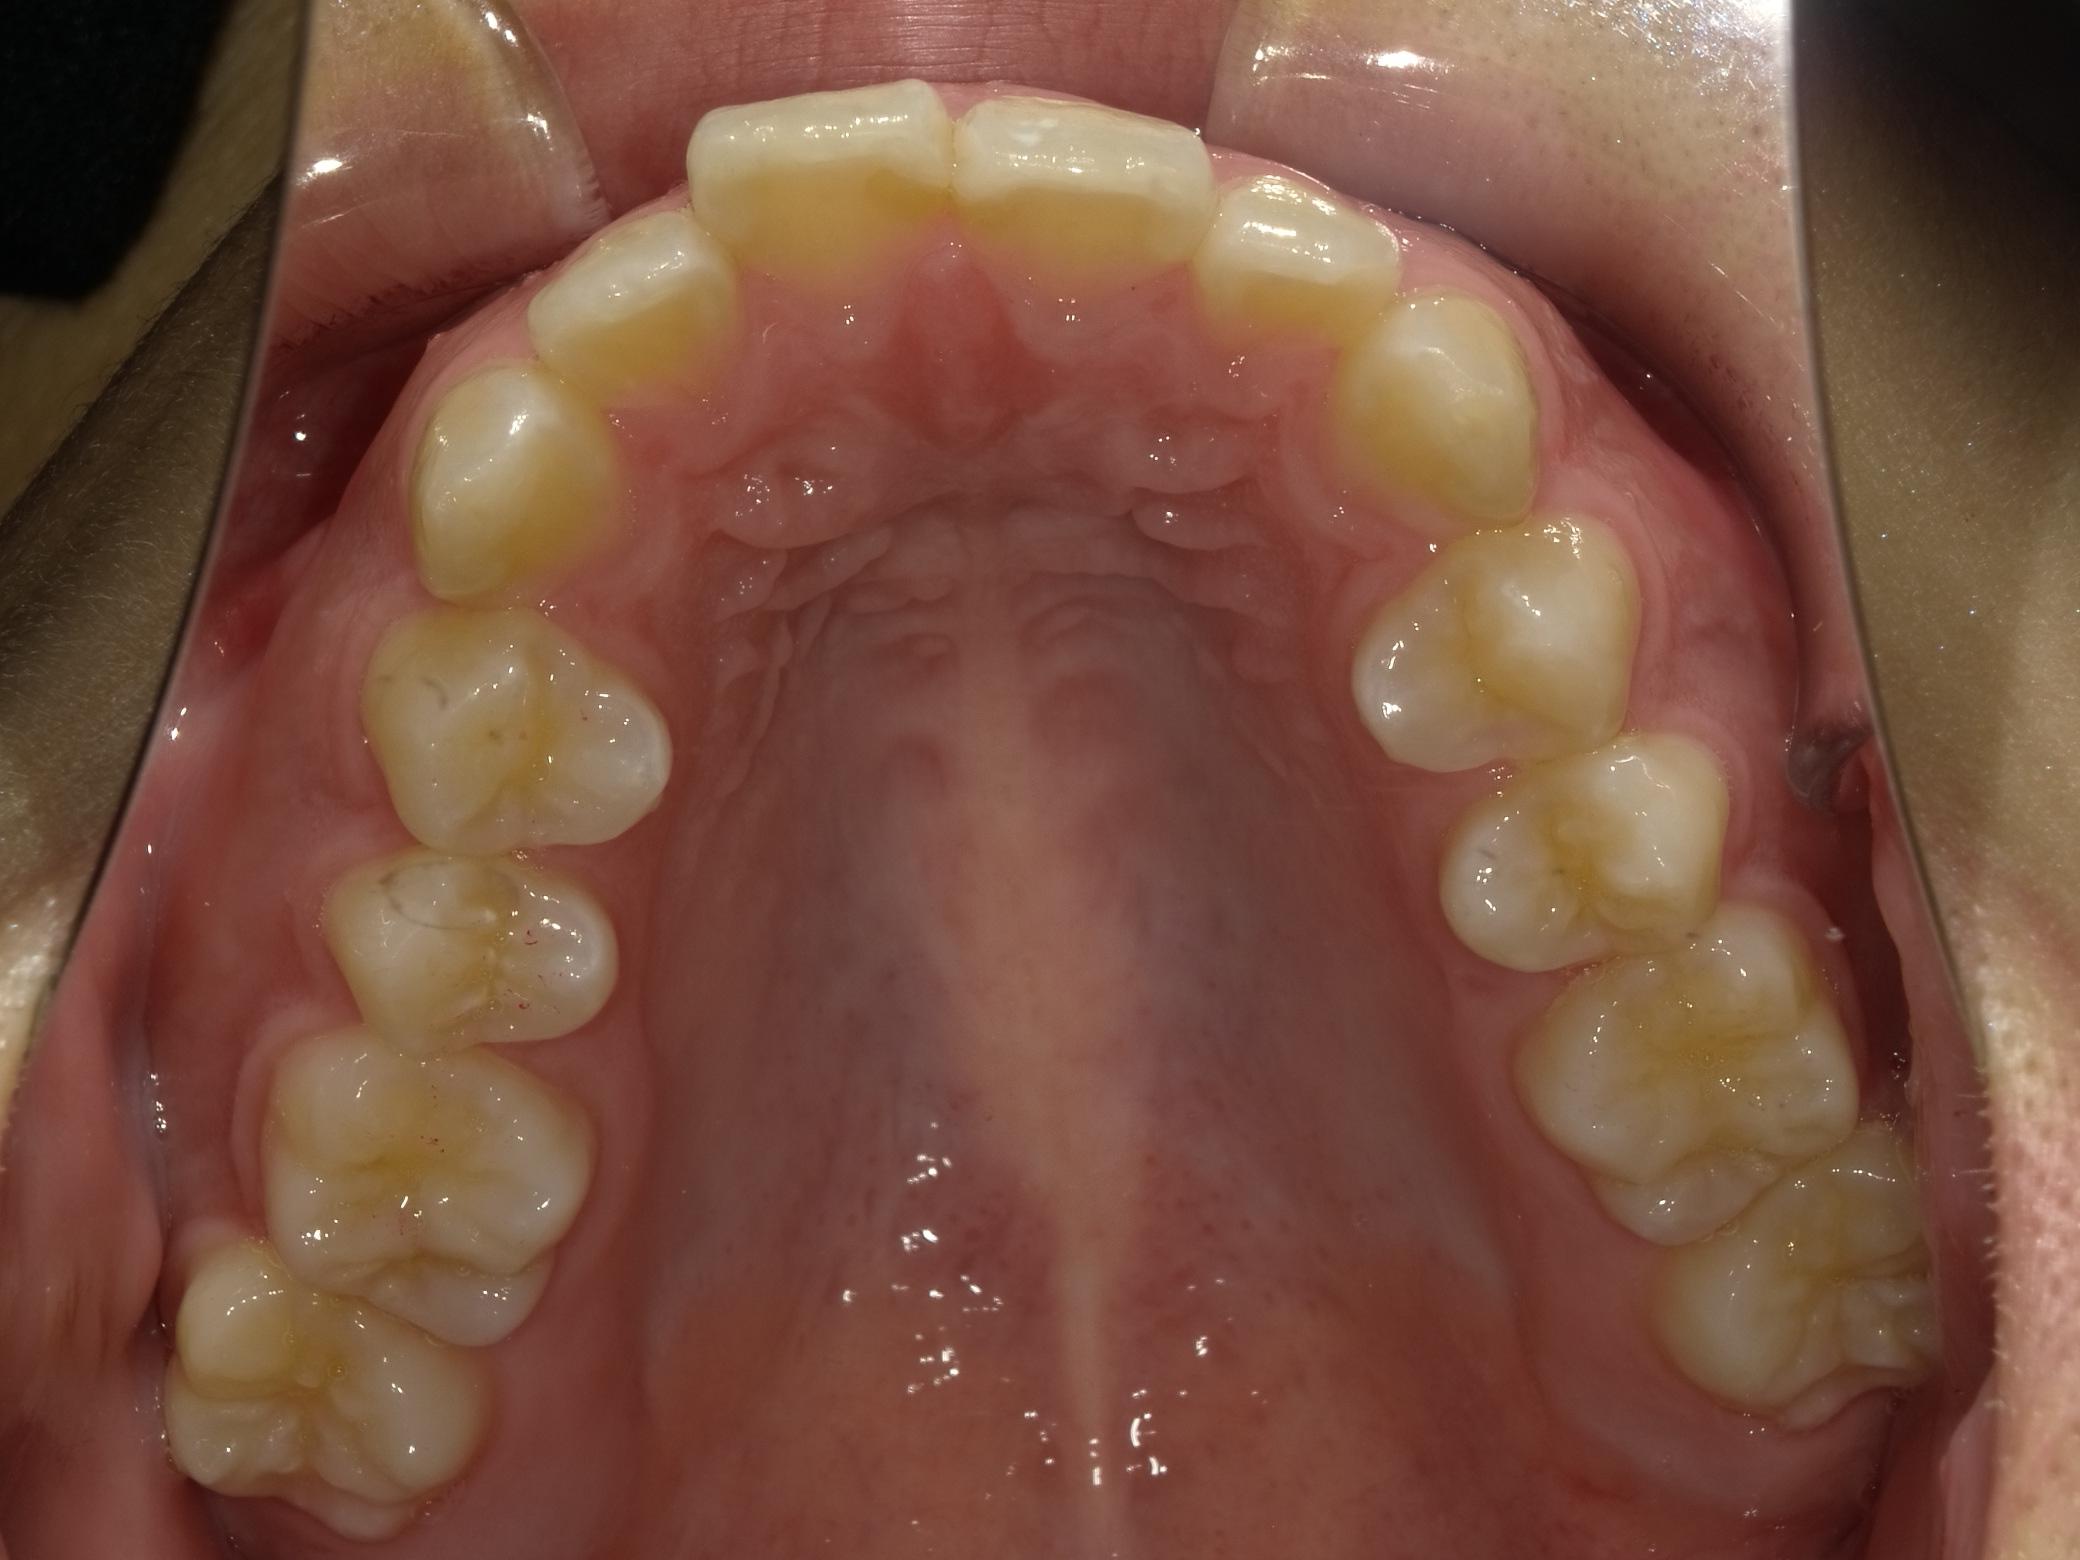

マウスピース矯正やワイヤー矯正に加え、必要に応じてアンカースクリューを活用することで、より複雑で難しい歯並びの症例にも対応しています。これにより、従来の矯正だけでは難しかった歯の移動も可能となり、幅広い治療の選択肢をご提供できます。

症例

矯正歯科専門の歯科医師が専門的な知識と確かな実績を

もとに患者様にあった最適な治療プランをご提案します。